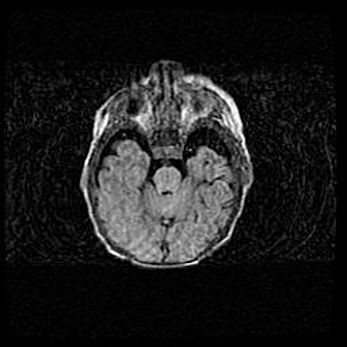

Открытая гидроцефалия.

Возраст: 9 месяцев 12 дней

Вес: 6800 г

Пол: мужской

Окружность головы: 41,5 см

Срок гестации: 28 недель

Гидроцефалия головного мозга у новорожденных имеет характерный признак: опережающий рост окружности головы приводит к визуально хорошо определяемой гидроцефальной форме сильно увеличенного в объёме черепа. Детские неврологи определяют следующие симптомы гидроцефалии у грудничков: выбухающий напряжённый родничок, частое запрокидывание головы, смещение глазных яблок к низу.